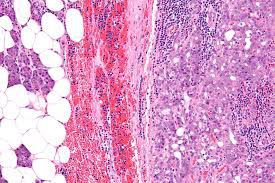

Acinic cell carcinoma is an uncommon low-grade malignant tumor of the salivary glands, in which some cells resemble normal acinic cells. Most of these tumors occur in the parotid gland. Women are affected more often than men, and the age at occurrence is earlier than in other salivary gland cancers.